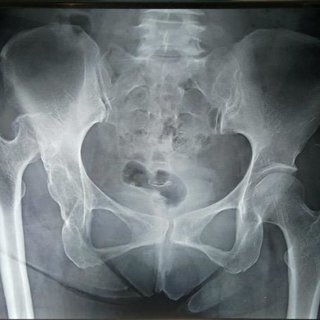

Q

Patient presents with worsening hip pain following MVA 6 months ago where he did not seek medical attention.

1. Describe what you see on his plain radiograph.

2. What is your impression?

3. How will you manage him?

A

1. Management

Aims: to obtain a pain free and stable hip

THR with constraints component

https://www.ncbi.nlm.nih.gov/pmc/articles/PMC5653596/

Due to neglected hip, AVN is 100%

Global softening of femoral head after one year of neglected dislocation warrants replacement of the femoral head.